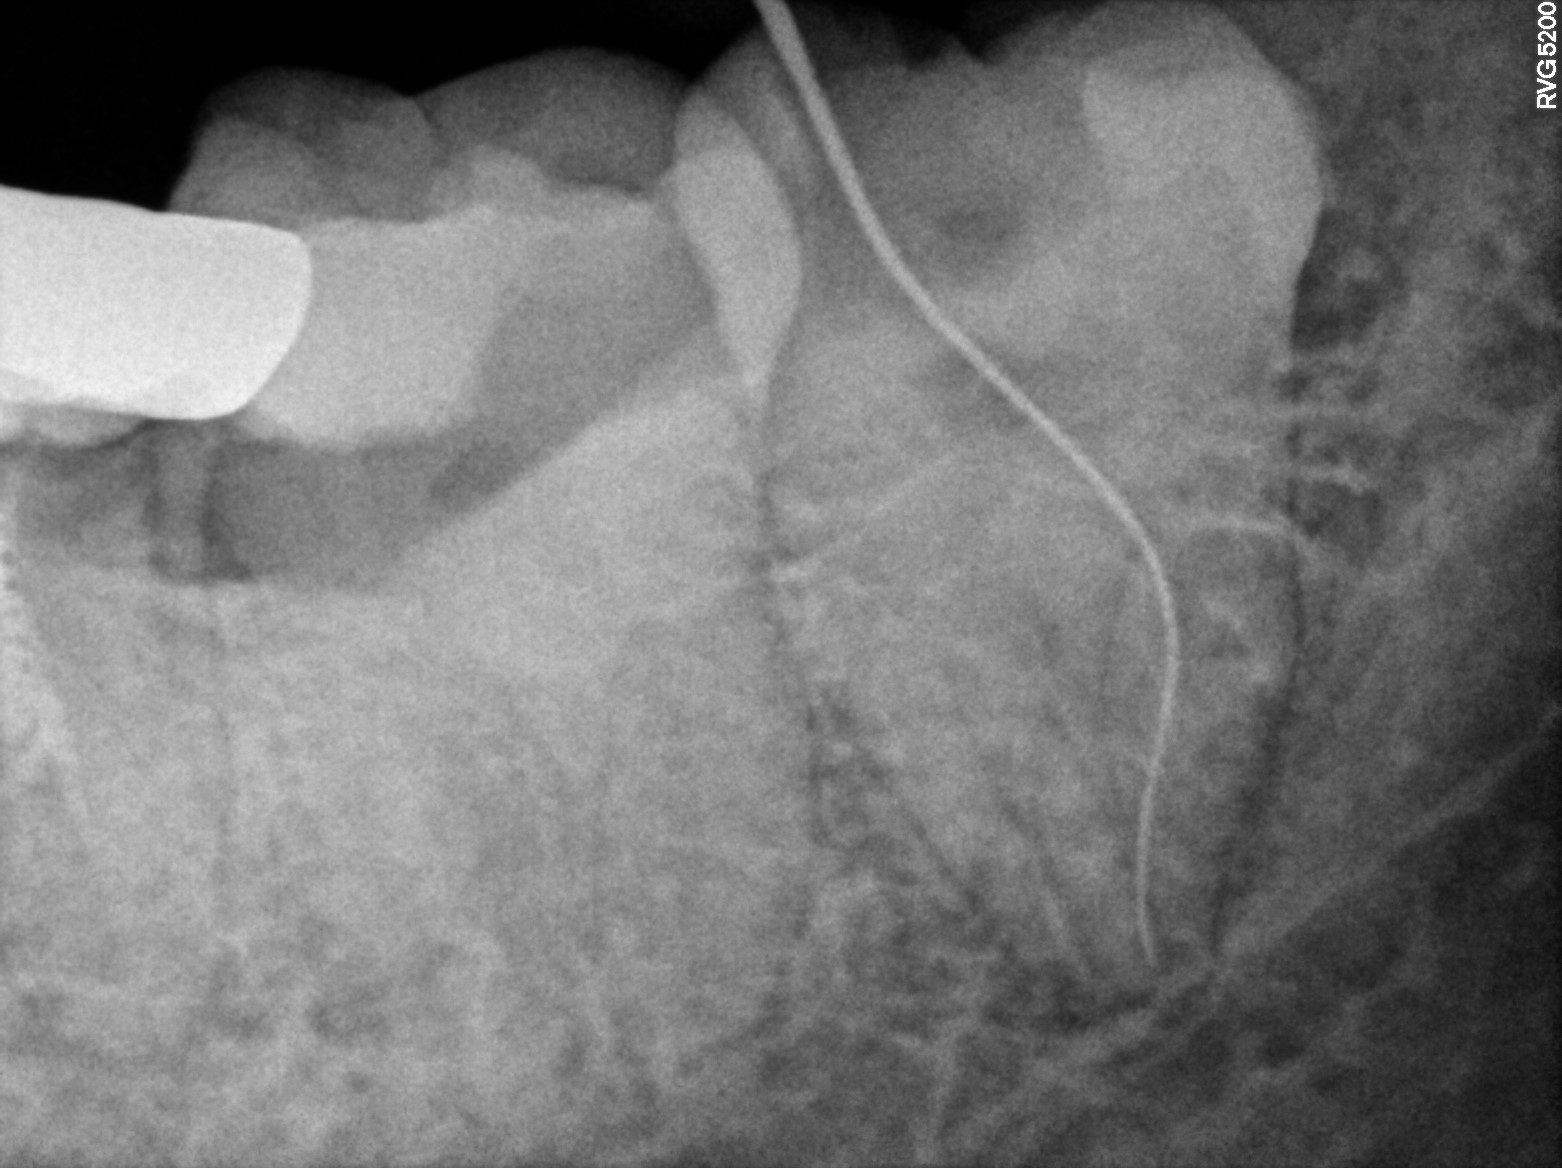

Dental Radiographs FHIR: DocumentReference · LOINC 24641-7

R38.jpg

24641-7